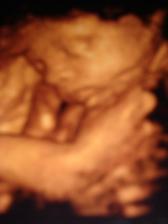

11.6.nás čaká ďalšia poradňa a veĺký ultrazvuk,aby sme vedeli,koľko ten náš macík váži 🙂 tak Samko je hlavičkou dole,váži 1598g a všetko je v poriadku,zobrali nám krvičku na protilátky,tak verím,že to dopadne dobre,čípok nezmenený a hrdlo stále uzatvorené 🙂už teraz mi dáva slušné kopance a je to niekedy až neuveriteĺné,čo predvádza,keď naňho hovorí tatino 🙂